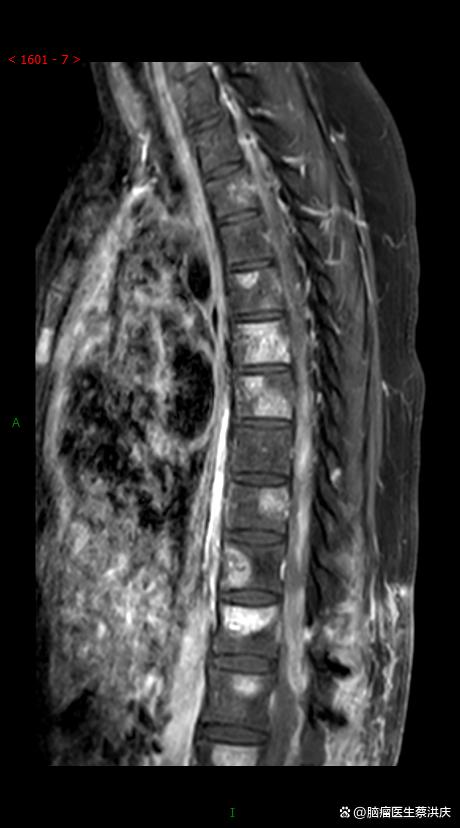

脑胶质瘤属于癌症范畴,但需结合其分类和分级具体分析脑胶质瘤起源于神经胶质细胞,是颅内最常见的原发性肿瘤,约占所有原发性颅内肿瘤的40%50%其本质是细胞异常增殖形成的肿瘤,符合癌症“细胞失控性生长”的核心特征,因此从广义上可归类为癌症但需注意,脑胶质瘤的恶性程度差异显著,需通过分类。

胶质瘤属于癌症具体分析如下胶质瘤的本质是恶性肿瘤其起源于神经胶质细胞,这类细胞在中枢神经系统中承担支持和保护神经元的功能胶质瘤作为中枢神经系统最常见的原发性肿瘤,约占所有颅内肿瘤的50%,且被明确归类为恶性肿瘤胶质瘤符合癌症的核心特征癌症的本质是异常细胞失控生长并扩散,而胶质瘤。

胶质瘤属于癌症范畴,是颅内最常见的恶性肿瘤胶质瘤常被称为“脑癌”,其占所有颅内肿瘤的40%~50%,这一比例体现了它在脑部肿瘤中的高发性从病理性质来看,胶质瘤的本质是恶性肿瘤,具有侵袭性生长和潜在转移的特性,这与癌症的生物学行为一致胶质瘤的恶性程度通过分级系统明确划分,共分为4级。